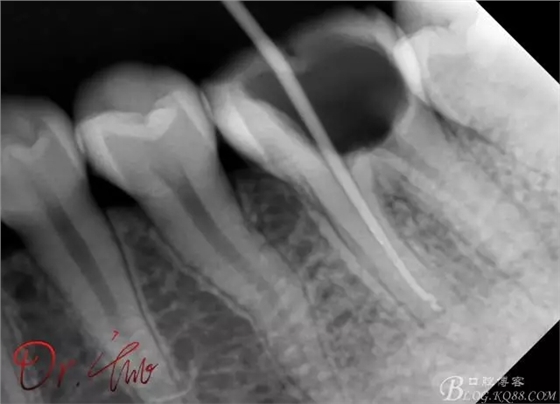

最后根充,明顯可看到臺階位置,期待預(yù)后效果

歡迎各位老師來拍磚指導(dǎo)